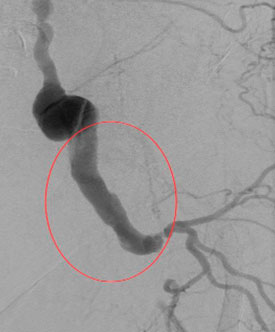

В отделении ССХ клиники ЦЭЛТ выполнена ангиография нижних конечностей

Обследование в отделении сердечно сосудистой хирургии подтвердило сложное, многоуровневое поражение артерий левой нижней конечности: аневризма наружной подвздошной и общей бедренной артерий, закупорки и сужения были обнаружены на всем протяжении – от подвздошных артерий в малом тазу до мелких сосудов голени. Кровоток до стопы доходил в малом количестве, через обходные пути (коллатерали).

Значимый стеноз общей подвздошной артерии, аневризматически расширенная наружная подвздошная артерия |

Аневризматичски расширенная общая бедренная артерия, окклюзия поверхностной и глубокой бедренной артерий |